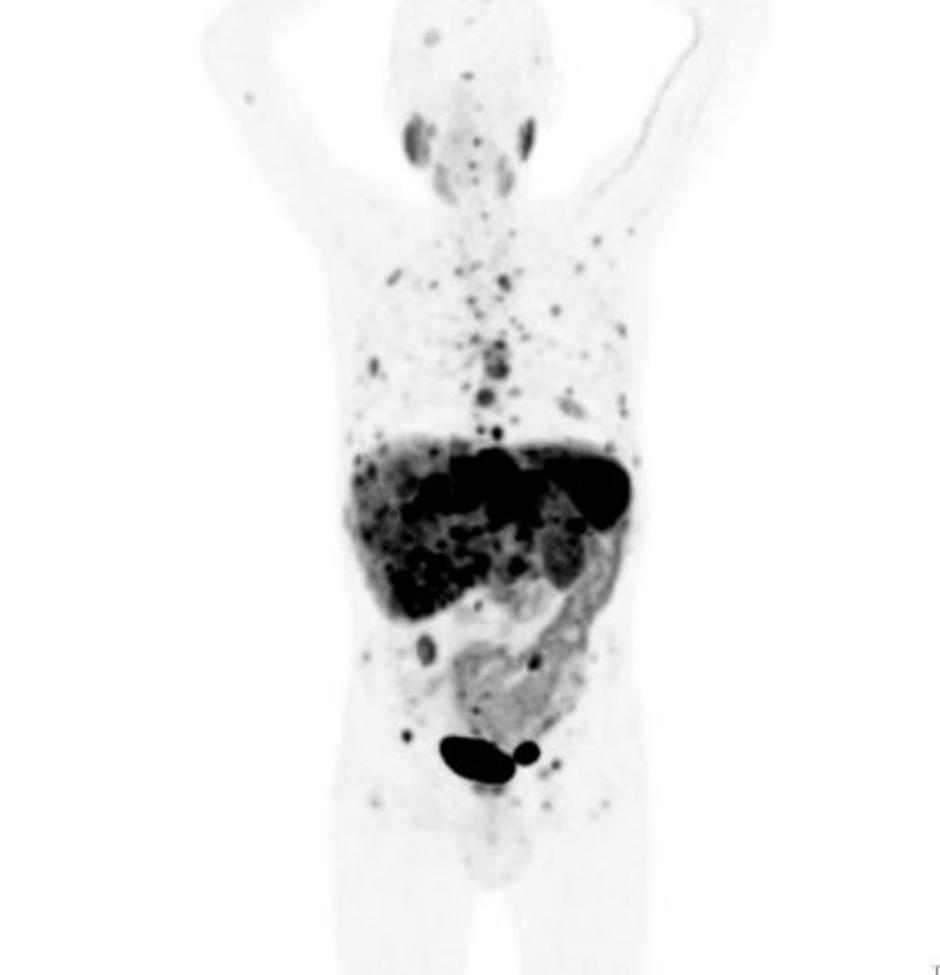

Na kliniki za nuklearno medicino Univerzitetnega kliničnega centra (UKC) Ljubljana so v teh dneh predstavili nov diagnostični pristop ugotavljanja prisotnosti in razširjenosti nevroendokrinih tumorjev ter spremljanju učinkovitosti zdravljenja teh bolnikov.

V UKC Ljubljana je tako na voljo najboljša metoda diagnostike nevroendokrinih tumorjev doslej. S pomočjo PET/CT preiskave, pri kateri uporabijo galij-68, se lahko pravočasno postavi diagnozo, oceni stanje bolezni in izbere najboljše zdravljenje oziroma zazna spremembo bolezni. "Navadno odkrijemo od 65 do 70 odstotkov nevroendokrinih tumorjev, z novo metodo z galijem-68 pa jih

odkrijemo 90 odstotkov ali več. Gledano globalno je to najbolj učinkovita diagnostika,"

je povedal doc.dr. Luka Ležaič iz Klinike za nuklearno medicino.

Odkrivanje nevroendokrinega tumorja (NET), redke vrste raka, za katero je umrl nekdanji predsednik uprave podjetja Apple Steve Jobs in ki se pogosto zamenjuje z bolj agresivnim rakom trebušne slinavke, je težko in zapleteno. Bolezen namreč poteka z neznačilnimi simptomi, včasih jih sploh ni, pojavijo pa se tudi takšni simptomi, ki lahko kažejo na druge bolezni.